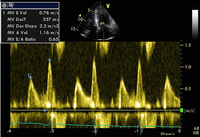

Pseudonormalização de fluxo de entrada mitral do E:A

Do acervo de Dr Jessica Webb; usado com permissão